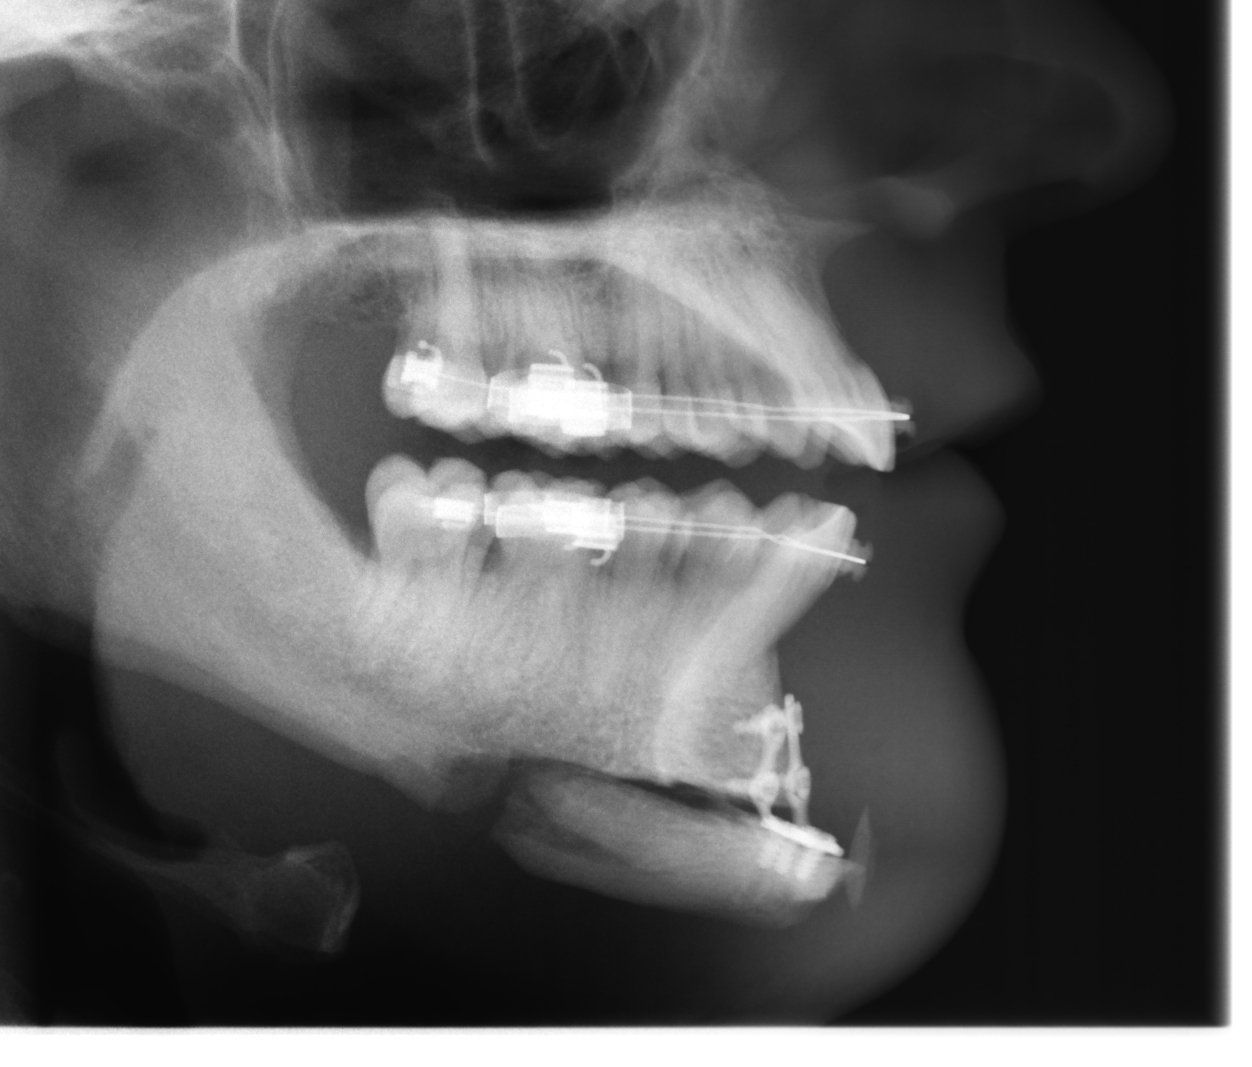

Die Kinnplastik

Eigenknochen kann gesägt, verschoben und entfernt werden. Kunststoff kann eingebracht und ausgetauscht werden. Der Zugang ist der Zahnfleischrandschnitt. In der Regel erfolgt die Operation in Narkose.